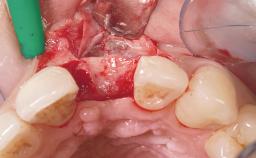

Soft Tissue Grafting | Simultaneous |

Soft Tissue Contour and Volume | Slightly compromised |